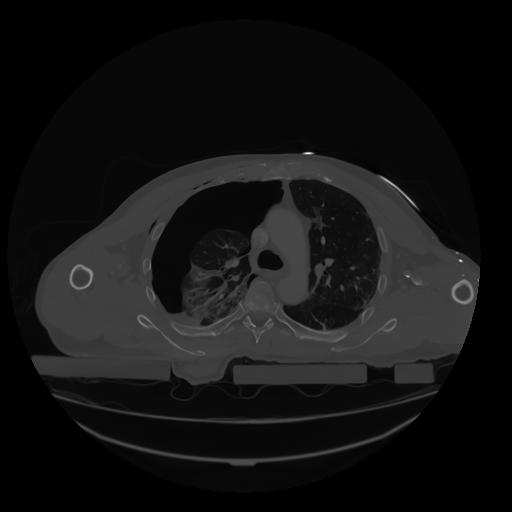

28 CUERPO,CE,Vol,2.0,CUERPO,,